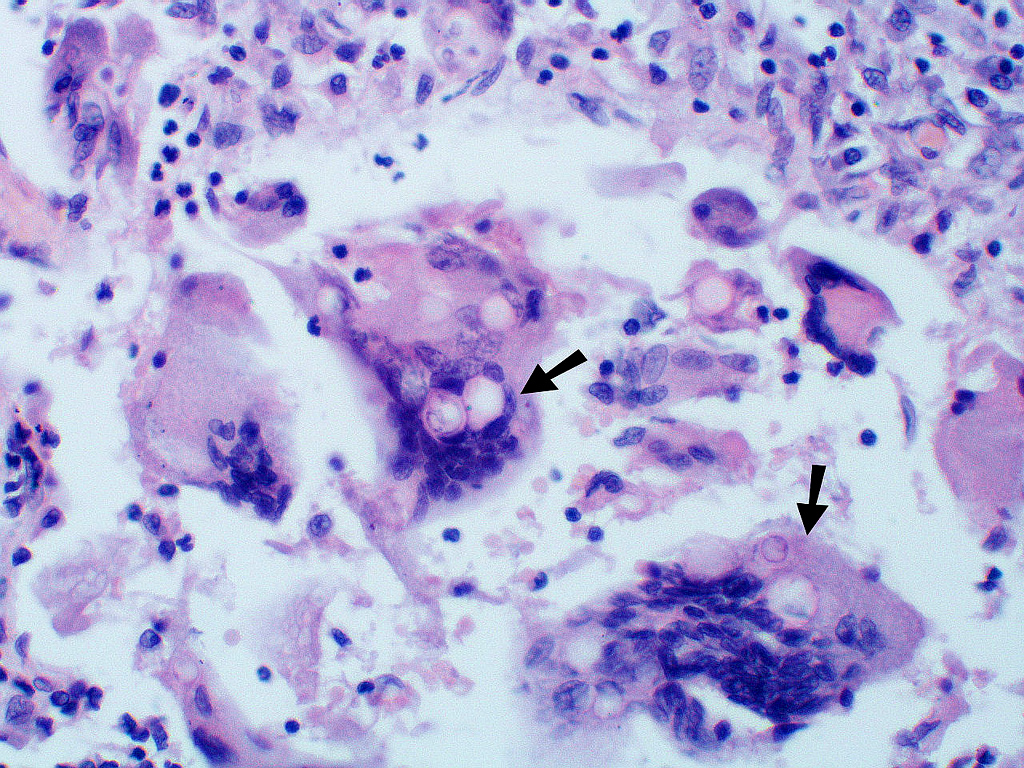

![Blastomycosis Americana (click on photo to enlarge) [source: Yale Rosen - Wikimedia - Creative Commons License 2.0] Blastomycosis Americana](../../../images/north-american-blastomycosis-3z.jpg) |

![Blastomycosis Americana (click on photo to enlarge) [source: Yale Rosen - Wikimedia - Creative Commons License 2.0] Blastomycosis Americana](../../../images/north-american-blastomycosis-4z.jpg) |

Blastomycosis Americana |

PA-foto's links: Yale Rosen (Wikimedia - Creative Commons License

2.0)

Zie ook de ingescande PA-coupes (

coupe

1,

2) van de

afdeling pathologie

van de University of Toronto.